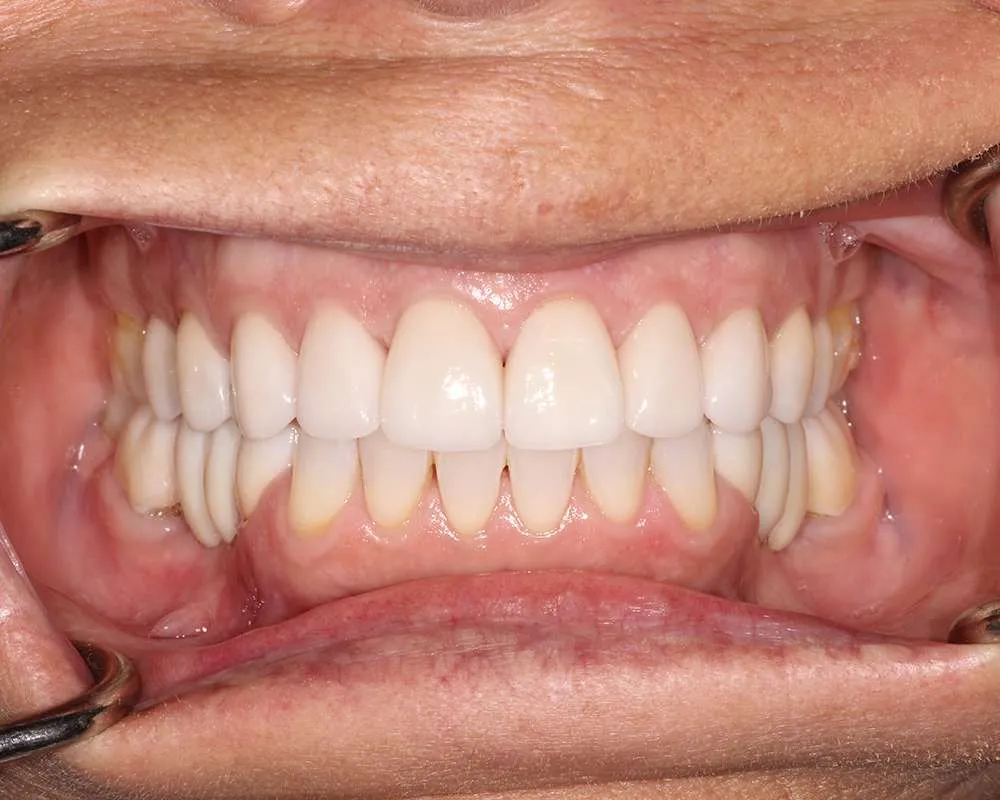

Real Stories, Real Results: Case Studies Showcasing How Our Personalized Approach Transforms Smiles and Lives

Witness the Remarkable Changes We Can Achieve